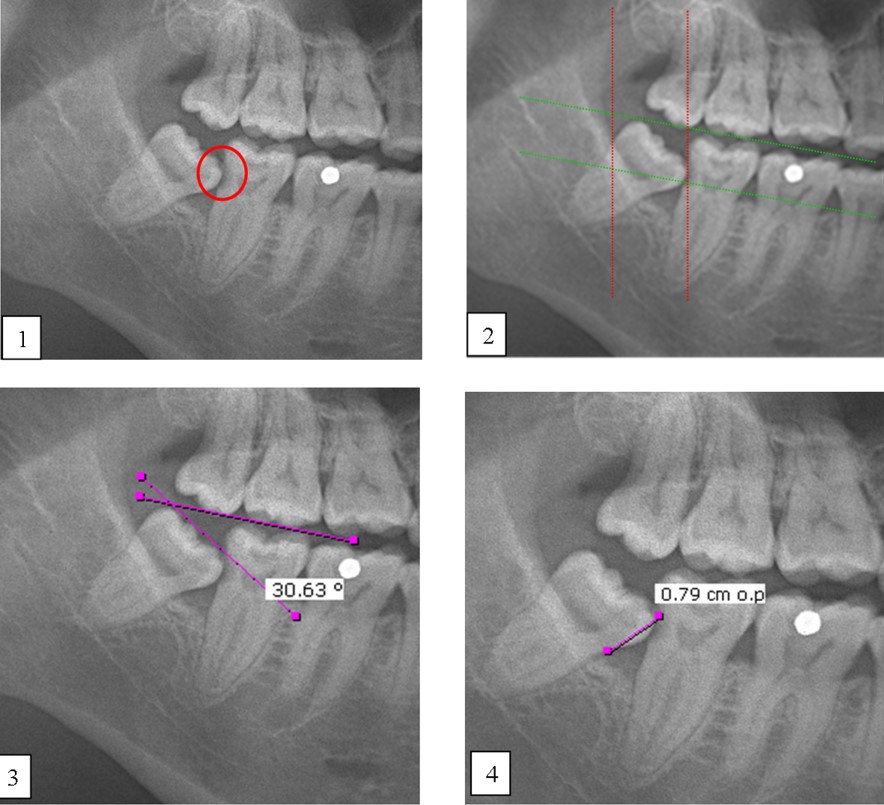

One of the notable complications of impacted mandibular third molar (MTM) is distal caries of the mandibular second molar (MSM) which can eventually lead to its early loss. The present study aimed to investigate the incidence of dental caries in MSM associated with impacted MTM and to propose an assessment protocol for MTM management. Patients’ dental records with dental panoramic tomography (DPT) imaging were studied retrospectively, in total 583 MTM images were evaluated. The presence of MSM distal caries, patient’s details, impaction depth, pattern and angulation of MTM and the distances between distal MSM and mesial MTM were assessed. Logistic regression analysis was performed on the data set. The highest caries incidence was observed in mesioangular impacted MTM (34.1%). Majority of the caries found were Level A (27.9%) and Class II (27.0%). The highest distance between distal MSM and MTM contributing to caries was 0.70-0.99 cm (31.9%). Patients’ age, angulation, pattern and depth of impacted MTM are the predictors which significantly increase the caries incidence in MSM (p<0.05). Prophylactic removal of MTM should be proposed when the distance of mesial impacted MTM and distal MSM is around 0.70-0.99 cm, and is mesially angulated with IIA classification.

Salah satu komplikasi ketara gigi geraham bongsu rahang bawah (MTM) yang tidak tumbuh sepenuhnya (terimpak) ialah karies distal pada geraham kedua rahang bawah (MSM) yang akhirnya boleh menyebabkan kehilangan awal gigi tersebut. Kajian ini bertujuan untuk menyiasat kejadian karies gigi pada MSM yang mempunyai kaitan dengan MTM terimpak serta cadangan penilaian langkah pengurusan berkaitan dengan MTM. Rekod pergigian pesakit bersama gambar panoramik pergigian telah dikaji secara retrospektif, dengan sejumlah 583 imej MTM telah dinilai. Kewujudan karies distal MSM, butiran pesakit, kedalaman impaksi, corak dan sudut MTM serta jarak antara MSM distal dan MTM mesial telah dinilai. Analisis regresi logistik dijalankan ke atas set data. Insiden karies tertinggi diperhatikan pada MTM terimpak mesioangular (34.1%). Kebanyakan karies yang ditemui ialah Tahap A (27.9%) dan Kelas II (27.0%). Jarak tertinggi antara MSM distal dan MTM yang menyumbang kepada karies ialah 0.70-0.99 cm (31.9%). Umur pesakit, sudut, corak dan kedalaman MTM terimpak ialah pembolehubah yang meningkatkan insiden karies pada MSM secara signifikan (p<0.05). Cabutan pencegahan gigi MTM sepatutnya dicadangkan apabila jarak antara MTM terimpak mesial dan MSM distal adalah sekitar 0.70-0.99 cm, dan MTM bersudut mesial dengan klasifikasi IIA.